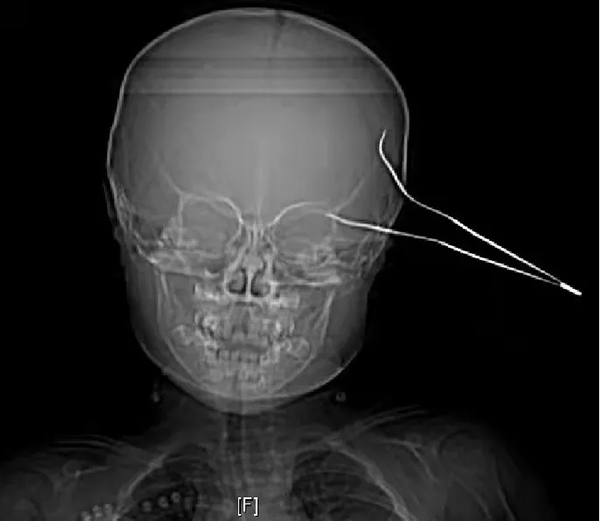

徐醫(yī)附院:15cm鑷子直插兩歲女童大腦,神經(jīng)外科成功救治,患兒轉(zhuǎn)危為安

患兒笑笑(化名)是一位天真活潑,率真可愛的女孩,在父母的呵護(hù)下快樂成長。然而,天有不測風(fēng)云, 10月23日中午10時許,笑笑在玩鬧過程中不慎摔傷,致15cm長的金屬鑷子刺入頭部,當(dāng)時傷口少量出血,笑笑因疼痛哭鬧不止,家人將笑笑緊急送至當(dāng)?shù)蒯t(yī)院,頭顱CT示左側(cè)顳部條狀致密影穿透左側(cè)顳骨,深入左側(cè)顳葉,情況十分危急,當(dāng)?shù)蒯t(yī)院建議轉(zhuǎn)至徐醫(yī)附院進(jìn)行手術(shù)治療。

徐醫(yī)附院急診醫(yī)護(hù)人員接診后,立即聯(lián)系神經(jīng)外科值班醫(yī)生進(jìn)行會診。神經(jīng)外科醫(yī)師張桐會診發(fā)現(xiàn),笑笑左側(cè)顳部金屬質(zhì)鑷子兩支齒的尖端均深入皮下,余在外的鑷子底部已經(jīng)嚴(yán)重彎曲變形,由此可見患兒受傷時所受外力之大。張桐醫(yī)師查閱CT后立即向凌南主治醫(yī)師及劉勇主任醫(yī)師緊急匯報。劉勇主任團(tuán)隊經(jīng)過綜合討論和全面評估,認(rèn)為需要立刻進(jìn)行手術(shù),取出腦部異物,以免引發(fā)二次傷害和顱內(nèi)感染,于是,快速啟動醫(yī)院綠色救治通道、與患兒家長溝通、聯(lián)系手術(shù)室進(jìn)行術(shù)前準(zhǔn)備、聯(lián)合多學(xué)科進(jìn)行保障……一場與死神的賽跑正式開啟。